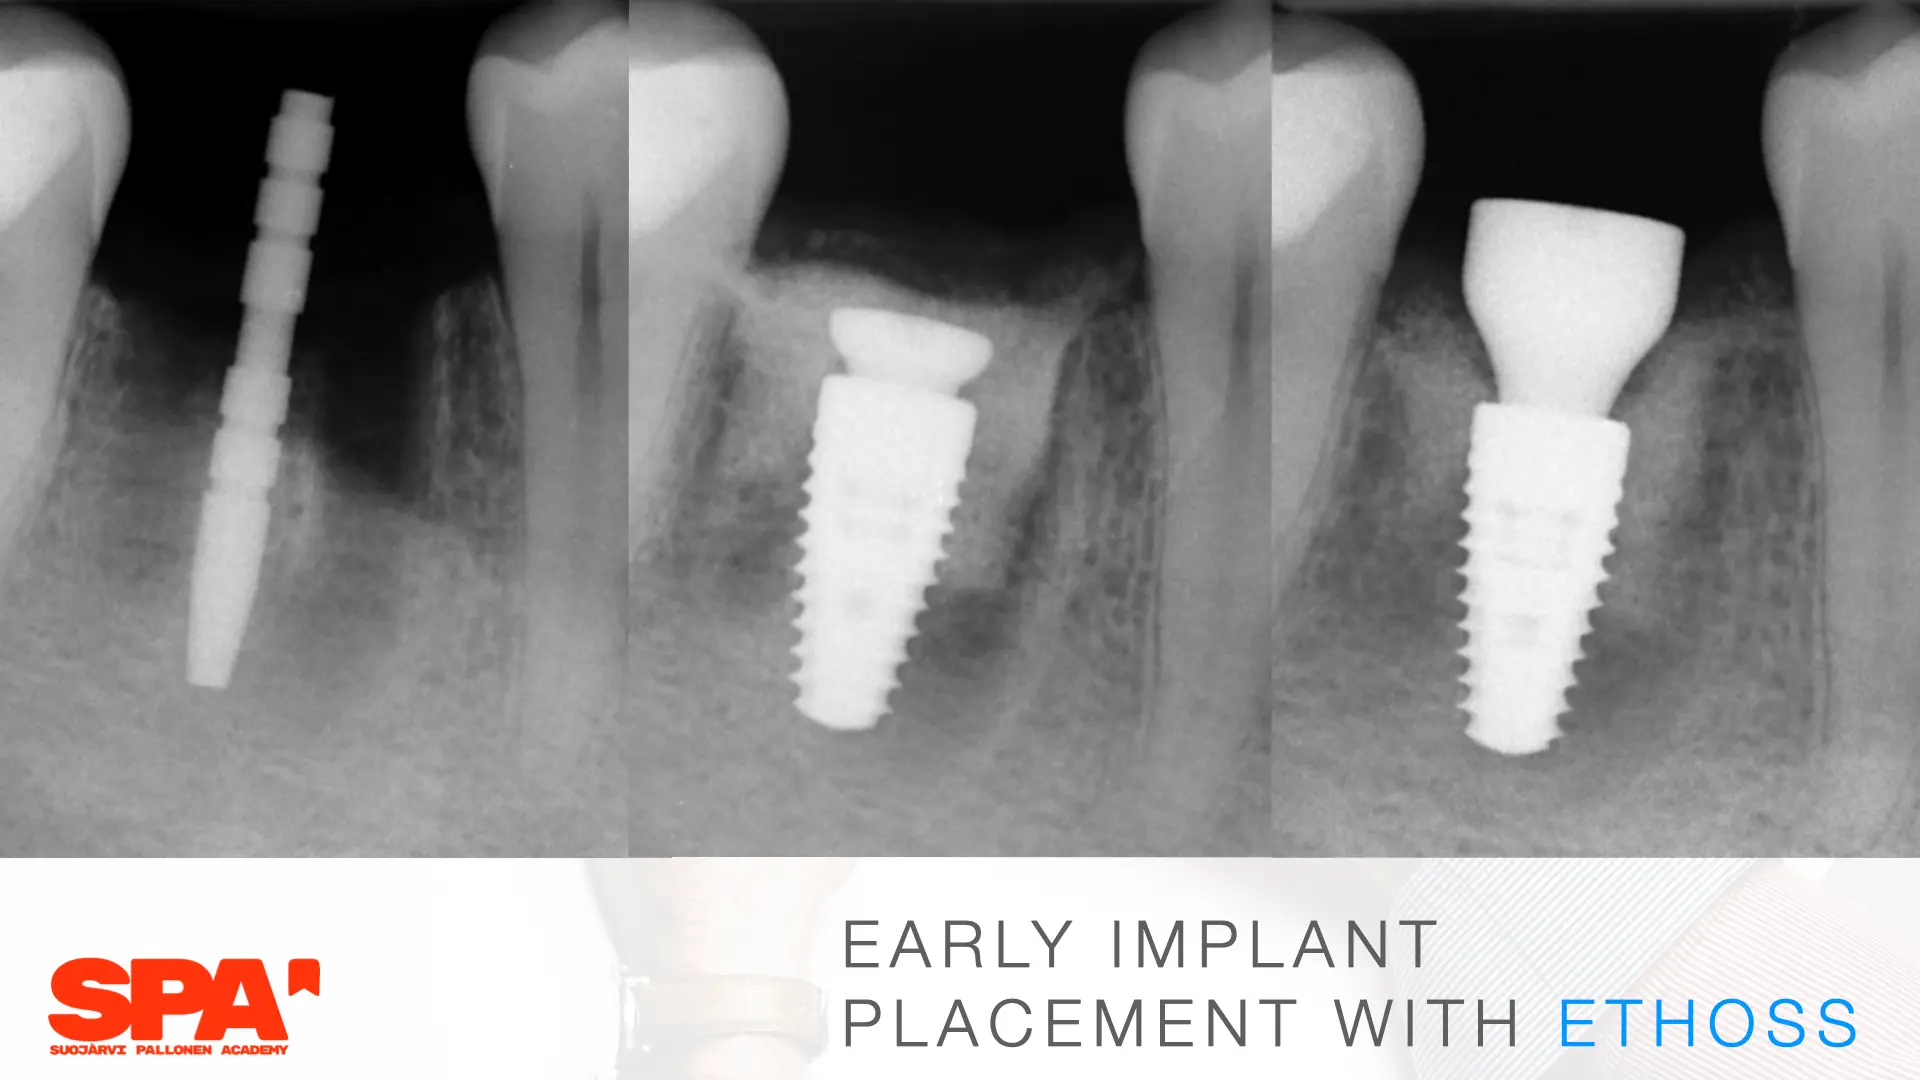

Seminaariesitykset keskittyvät täysin synteettiseen EthOss-biomateriaaliin, joka on kehitetty edistämään potilaan omaa luun uudistumista hammasimplanttien ja suukirurgian yhteydessä. EthOss koostuu β-trikalsiumfosfaatista ja kalsiumsulfaatista, jotka luovat ihanteelliset olosuhteet luun kasvulle ilman sulamattomia vieraspartikkeleita tai eläinperäisiä aineita, korvautuen kokonaan elävällä isäntäluulla noin 6–12 kuukaudessa.

Esityksissä käsitellään materiaalin valmistelua, käyttöä luusiirteissä sekä kliinisiä tuloksia, kuten nopeaa luunmuodostusta (jopa 50 % uutta luuta 12 viikossa), ilman tarvetta erilliselle kollageenikalvolle.

This lecture will explore how surgical simplicity combined with biologically active materials can achieve outstanding results across a range of indications — from socket preservation and regeneration to sinus lifting. Through clinical cases and practical protocols, Dr. Stuart Kilner will demonstrate how to optimise handling, improve efficiency, and achieve stable regeneration by working with, not against, the body’s innate capacity to heal.

EthOss cases by Dr Stuart Kilner

EthOss cases by Dr Ilkka Pallonen